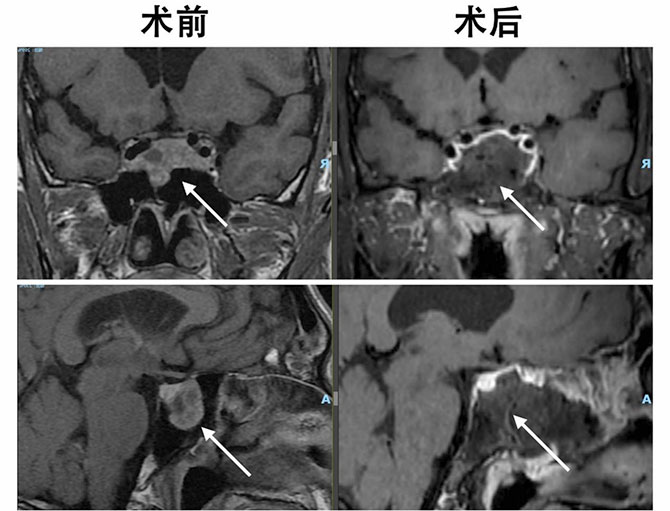

患者术前及术后垂体MR增强影像

刚进院时,患者李先生的症状已经十分明显,头痛难以入睡,满脸痤疮,而且手脚肥大。完善相关检查后,郭文龙主任诊断李先生颅内长有泌乳素和生长激素混合型垂体瘤,体积较大,且侵袭明显,累及双侧海绵窦及颈内动脉。郭主任建议采取微创的方法,通过神经内镜经单鼻腔全切肿瘤。该项技术优势在于,神经内镜抵近观察、角度灵活多变的特点不仅使手术更加微创,还大大增加了肿瘤全切的机会,同时经单鼻孔手术为患者保留了一个完整的鼻腔,术后鼻腔体验感明显提升,并发症少,恢复快,术后一般3-5天即可出院修养。